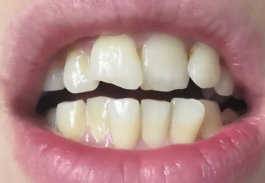

Виниры и голливудская улыбка

Добрый день, Мне 27 лет.

Хочу идеальную улыбку. Немного "расширить" челюсть. и выровнять зубы.

Вот фото зубов:

Возможно ли исправить винирами, и какими? Спасибо!